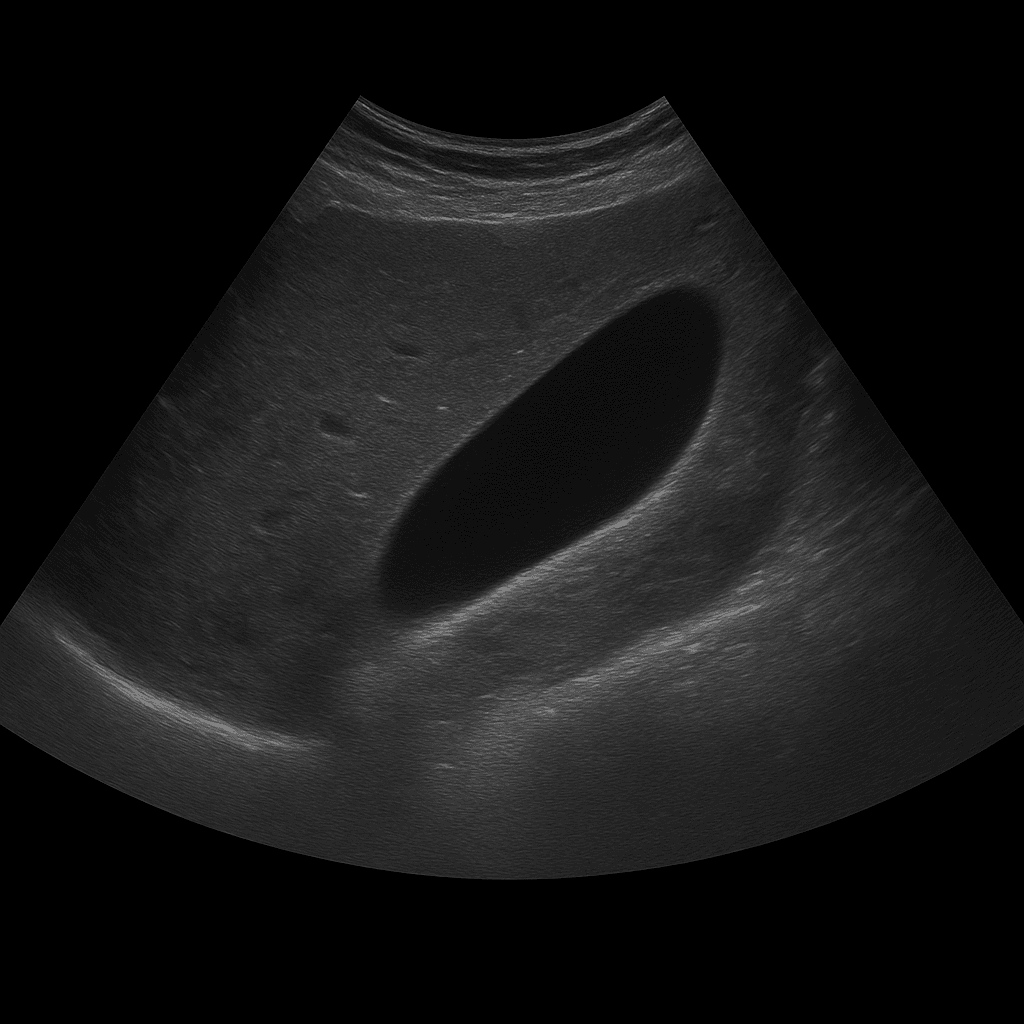

Ett ultraljud av gallblåsan används för att undersöka gallblåsans vägg, innehåll och funktion. Undersökningen utförs av specialistläkare inom radiologi och ger detaljerade bilder i realtid som visar om gallblåsan innehåller stenar, vätska eller tecken på inflammation. Ultraljud gallblåsa används som förstahandsmetod vid misstanke om gallstenssjukdom eller inflammation i gallblåsan (kolecystit).

Ultraljud gallblåsa rekommenderas vid smärta under höger revbensbåge, illamående, uppblåsthet eller återkommande obehag efter fettrik mat. Undersökningen kan visa om gallblåsan innehåller stenar, slam (gallgrus) eller förtjockad vägg som tyder på inflammation. Den används också för att följa upp tidigare gallstensbesvär eller efter operation där delar av gallvägssystemet finns kvar.

Till skillnad från ultraljud av gallvägar, som fokuserar på gallgångarna och deras förbindelse med levern, är ultraljud gallblåsa inriktad på själva gallblåsans vägg, innehåll och funktion. Metoden används för att upptäcka akuta eller kroniska förändringar i organet, medan MR eller DT används när man behöver bedöma gallgångar och omgivande organ mer i detalj.

Undersökningen utförs medan du ligger på rygg eller lätt på vänster sida. En gel appliceras på huden och läkaren för ultraljudsproben över området under höger revbensbåge. Undersökningen tar vanligtvis 10–20 minuter. För bästa bildkvalitet behöver du vara fastande i minst 4–6 timmar innan, eftersom en tom gallblåsa är svår att bedöma.